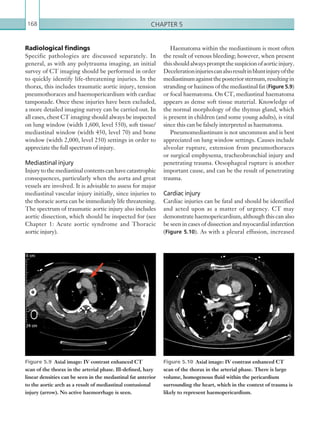

Figure 2.91  Axial image: IV contrast enhanced CT

scan of the pelvis in the portal venous phase. There are

enhancing, tubular structures within both adnexa, which

contain low density material consistent with bilateral